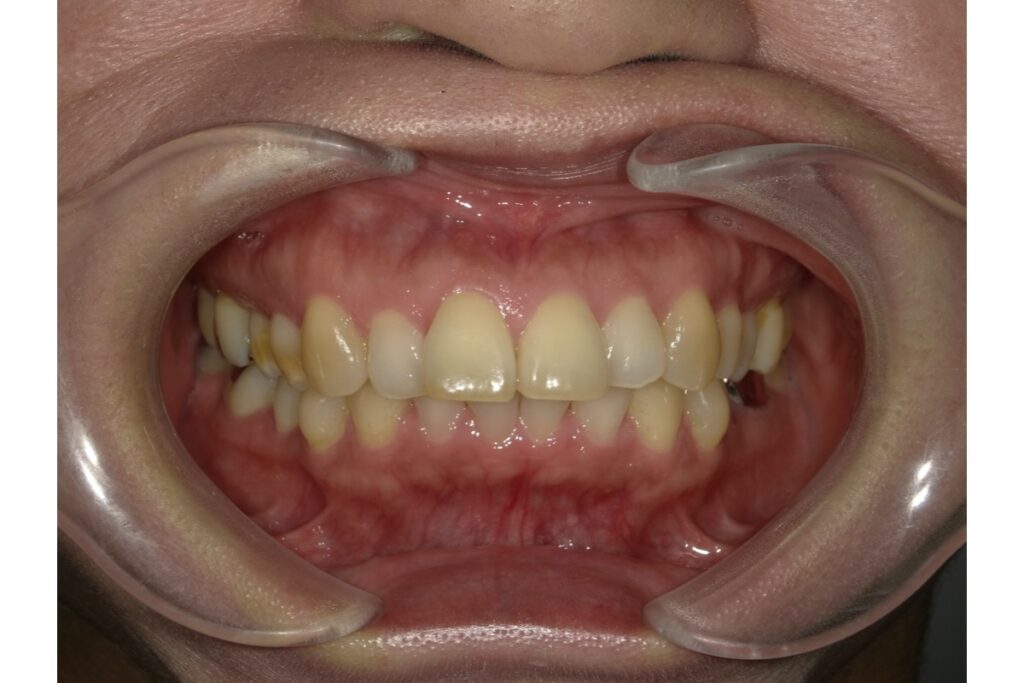

1. 重度の叢生(歯のデコボコ)

「叢生(そうせい)」とは、歯がガタガタに並んでいる状態を指します。特に顎の大きさに対して歯のサイズが大きすぎる場合、歯がきれいに並ぶスペースが足りずに重なって生えてしまうことがあります。

軽度の叢生であれば、非抜歯で歯列を広げたり奥歯を後ろに移動させたりして対応できますが、中等度〜重度の場合は抜歯によってスペースを確保する必要が出てきます。

抜歯矯正は、単に歯を並べるための手段ではなく、全体のバランスや将来の安定性まで考慮した矯正治療の一つの選択肢です。特に、叢生や出っ歯、開咬、口元の突出感などがある場合には、抜歯矯正が効果的なことも多くあります。